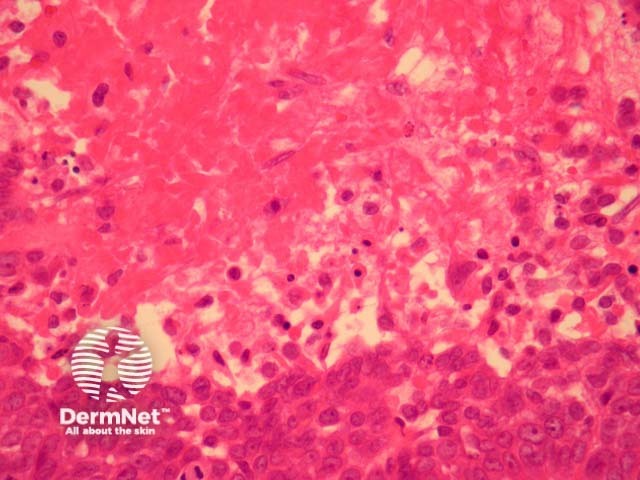

Hidradenocarcinoma may arise within a pre-existing hidradenoma. Hidradenocarcinomas are often large nodular dermally based tumours which may invade the subcutaneous fat (figure 1) and irregularly infiltrate the surrounding dermis (figure 2). The tumour cells are epithelioid and may often show clear cell changes (figure 3), or may appear basaloid, or have an eosinophilic cytoplasm (figure 1). There may be foci of squamous differentiation and duct formation (figure 2). There may be necrosis (figure 4).

Figure 3